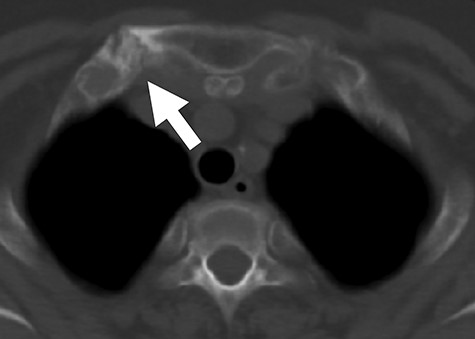

A-75-year old woman presented with arthralgia in both wrists, shoulders, upper limbs and ankles and complained of difficulties in walking and engaging in housework. She was diagnosed with SAPHO syndrome based on the dermatological manifestations (Fig. 1A) and thickened sternoclavicular joints (Fig. 2). Her symptoms did not respond to celecoxib, methotrexate or adalimumab, an anti-TNF-α drug. After bilateral tonsillectomy, her arthralgia and skin symptoms dramatically improved. Prior to tonsillectomy, the VAS, SF-MPQ-2 and PDAS scores were 30, 37 and 28, respectively. Three months after tonsillectomy, the methotrexate dose was reduced, and the patient showed significant improvements in her skin symptoms (Fig. 1B). The 3-month postoperative VAS, SF-MPQ-2 and PDAS scores were 20, 7 and 19, respectively. Six months after tonsillectomy, the patient no longer needed celecoxib. The VAS, SF-MPQ-2 and PDAS scores were 10, 4 and 24, respectively. Twelve months after tonsillectomy, the VAS, SF-MPQ-2 and PDAS scores were 5, 5 and 12, respectively. She could walk without the help of a stick 1 year after tonsillectomy (Fig. 3).

Axial CT image demonstrating thickened right sternoclavicular joint (white arrow). CT, computed tomography.